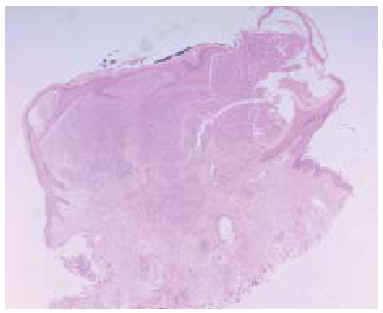

Fig. 2.--El estudio histológico mostró una proliferación lobulillar de capilares. (Hematoxilina-eosina, x40.)

Un niño de 15 años de edad, con el único antecedente de exéresis un año antes de un histiocitoma fibroso benigno localizado en la ceja derecha, consultó por una lesión tumoral exofítica de 5 mm de diámetro, de color rojizo, superficie lisa y friable al tacto, localizada en la zona clavicular izquierda. La lesión había aparecido un mes antes y había crecido de manera progresiva. Se realizó curetaje y electrocoagulación de la lesión. El estudio histológico de la pieza mostró una proliferación lobular de capilares que confirmó el diagnóstico de granuloma piogénico. A los 5 meses notó la aparición de cuatro nuevas lesiones de hasta 7 mm de diámetro, clínicamente similares a la tumoración previa, agrupadas en un área de 3 cm alrededor de la lesión extirpada anteriormente (fig. 1). Se realizó de nuevo curetaje y electrocoagulación de las lesiones sin recidiva en los 2 años posteriores. El estudio anatomopatológico fue idéntico al previo (fig. 2), sin observarse vaso nutricio en la profundidad de la lesión (fig. 3).